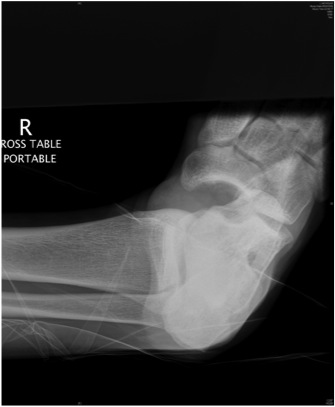

Subtalar Dislocation

Epidemiology

Rare

Types

Medial

- 80%

- calcaneum dislocated medially

Lateral

- 20%

- higher energy injury